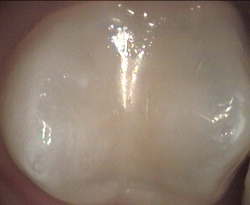

Top of back tooth

Restored